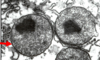

Identify

Peroxisome

- site of beta oxidation of LCFA (in addition to mitochondria)

- degrade hydrogen peroxide, a product of oxidative rxns

- Generate H2O2 = oxidase

- Break down H2O2 = catalase

- Synthesize cholesterol, plaminogens

What is outlined in red?

SER

site of synthesis and breakdown as needed of glycogen

note that the red arrow is pointing to glycogen shown as cluster of indv particles